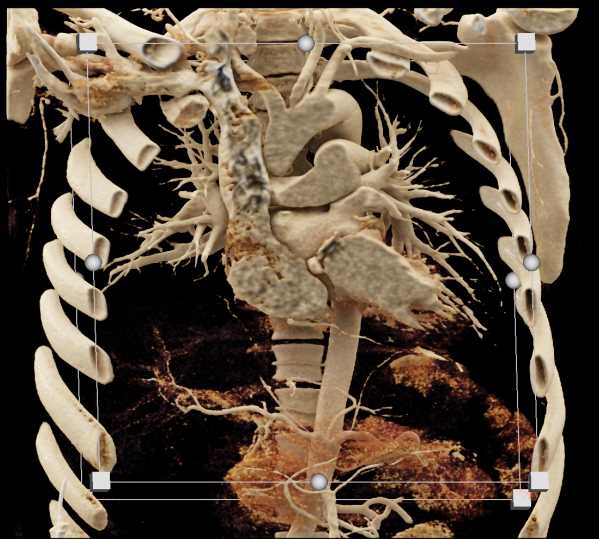

Aortic Valve Repair